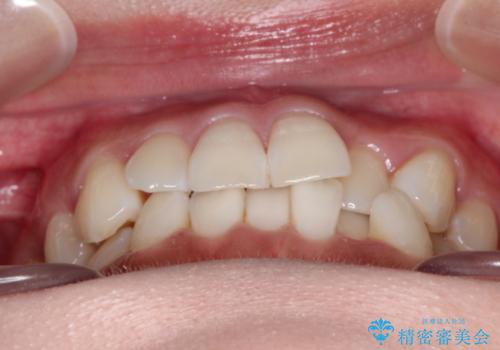

前歯のがたつきと反対咬合 インビザラインによる矯正治療

- 前歯のがたつきと反対咬合を主訴に来院されました。

下の前歯のがたつきを改善するために、右下の奥歯を後方に移動させるのと、歯と歯の間をわずかに削り、歯を並べる計画としました。

前歯の正中のずれを修正するのに少し時間がかかりましたが、整った歯並びにすることができました。